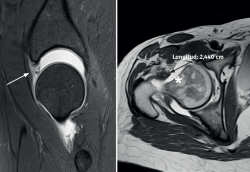

Se trata de una paciente mujer de 38 años de edad con antecedente de cirugía previa 3 años antes por choque femoroacetabular derecho que consultaba por presentar dolor residual. A la exploración, las maniobras de Faber e impingement eran muy positivas, así como el test de dial. Las maniobras de inestabilidad anterior (abducción y extensión) con aprehensión durante las maniobras suaves de rotación externa también eran positivas. No se evidenciaron anomalías rotacionales a la exploración. La puntuación en la escala modificada de Harris era de 68 puntos. Radiográficamente, el contorno en la unión cabeza-cuello era correcto, así como la cobertura acetabular. Se realizó adicionalmente una artrorresonancia magnética donde se evidenciaron áreas de degeneración/rerrotura condrolabral acetabular de 11-3 horaria y una cápsula articular deficiente de tipo 3 de la clasificación de Aoki(5) (Figura 1), sin alteraciones estructurales de versión en acetábulo y fémur, con gran desplazamiento a la distracción articular mediante tracción blanda, realizándose el diagnóstico de microinestabilidad de cadera posquirúrgica por pérdida del sello articular mixta capsular y labral. Bajo este diagnóstico, se propuso una reconstrucción labral y capsular simultánea por vía artroscopia.

Figura 1. Cadera derecha: artrorresonancia que muestra deficiencia labral y rerroturas (flecha) y defecto capsular importante (estrella) con gran desplazamiento articular a la tracción blanda.